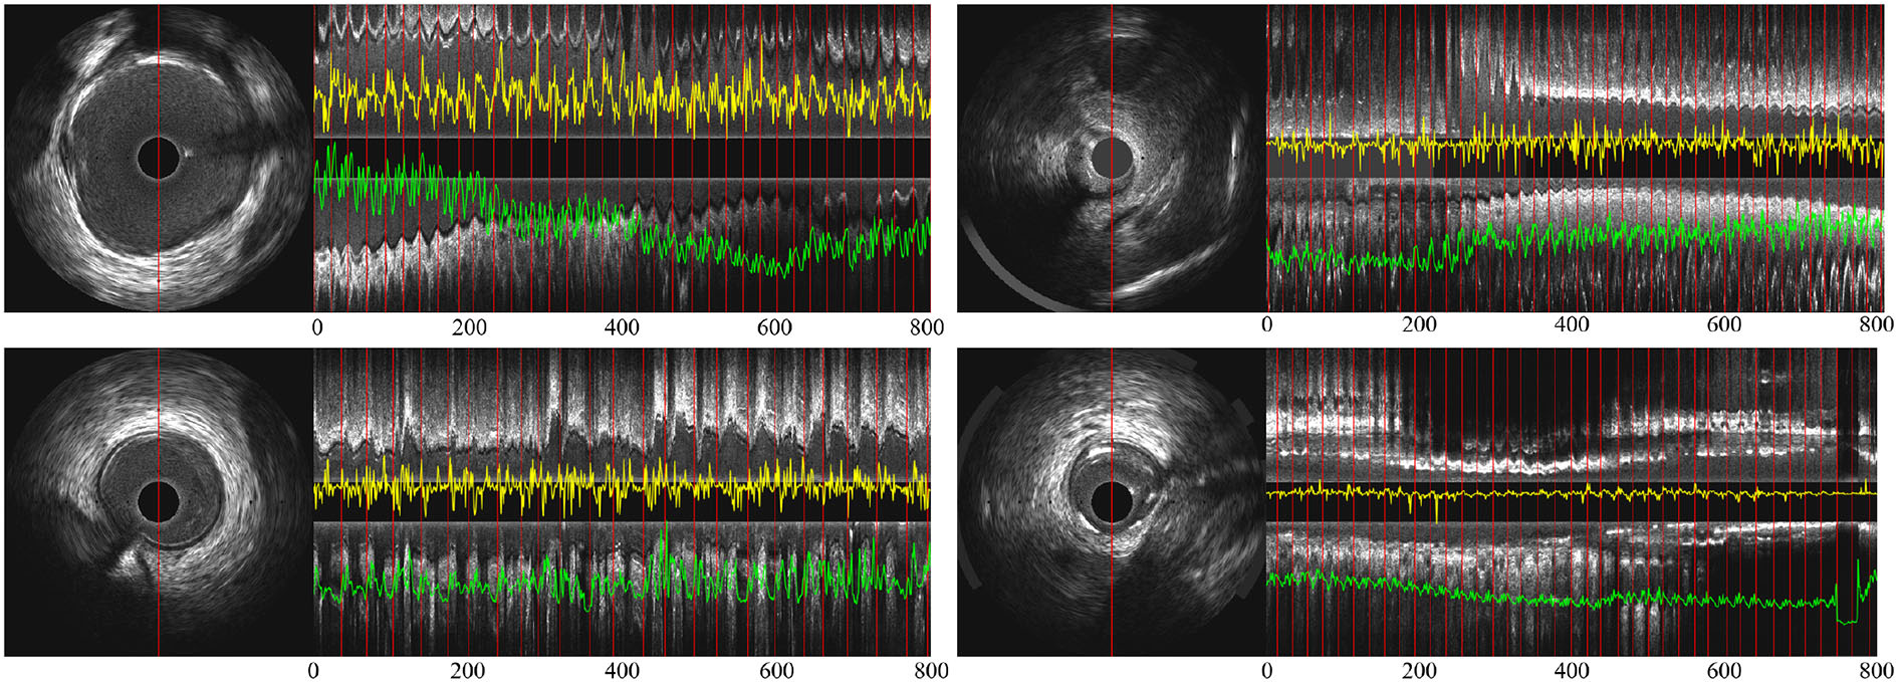

The artery motion captured by spatiotemporal rotation encoding is calculated for each two adjacent and aligned IVUS frames:Figure 5 shows the signals encoded by the temporal difference encoder and spatiotemporal rotation encoder, together with the corresponding longitudinal view for the original IVUS pullback. In the first three cases, the encoded signals from intense and regular cardiac motion show a clear cycle of motion between ED-frames, demonstrating the regular systolic relaxation of the heart. In the last case on the lower right, the movement of the vessel is small, and thus the coded movement feature is weak as well as vessel's rotation. The proposed temporal difference encoder and spatiotemporal rotation encoder transfers 2D image signal to 1D global temporal features to reduce the demand for GPU performance for ED-frame detection and eliminates the interference factors during data collection such as noise, rotation, and local diseases of vessels.

Figure 5

(A) Partial longitudinal views and the proposed encoded sequence in 4 IVUS sequences—the length of each partial longitudinal view is 800 frames (26.6 s). The image on the left is a representative IVUS frame with the red line showing the sampled pixels used in the partial longitudinal view (). The red lines in the longitudinal view indicate the ED-frames annotated by ECG. The yellow curves show the feature sequence encoded by the spatiotemporal rotation encoder and the green the temporal difference encoded sequence.